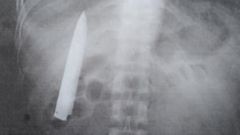

В январе прошлого года банда подростков порезала 25-летнего Кента Райана Томао в городе Кидапаван, Филиппины. Пострадавший был доставлен в государственную больницу, где лечащий врач зашил ему рану, но так и не сделал рентген. Он сказал, что рана выглядит не так уж и плохо и что парню повезло. Недавно для устройства на новую работу в шахту Томао потребовалось сделать снимок грудной клетки. На рентгене видно, что лезвие ножа так и осталось в груди.

«Я всегда удивлялся, когда чувствовал некоторую боль в груди в холодную погоду, но я и понятия не имел, что там все еще находится нож», — сказал Томао, слова которого приводит Daily Mail. Мужчина добавил, что травма беспокоила его только при перемене погоды, больше никаких симптомов не было.